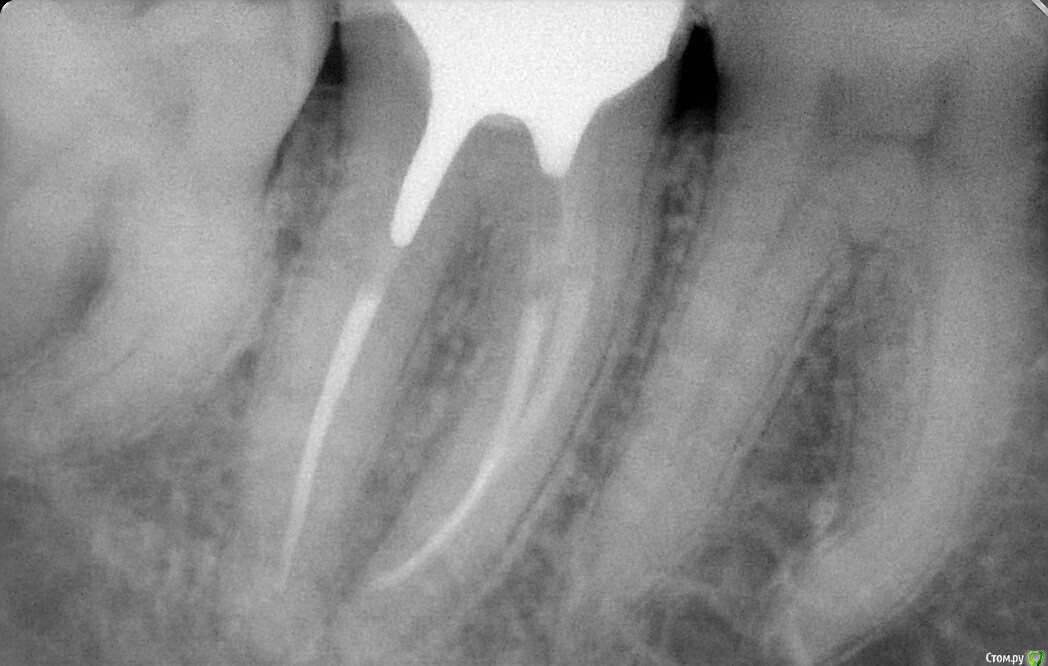

Antanta Опубликовано 25 ноября, 2018 Поделиться Опубликовано 25 ноября, 2018 Добрый вечер. Сделала огромную ошибку. Такие длинные корни и такой короткий штифт в дистальном канале получился. Вкладка сделана непрямым методом. С техником решили не делать штифты в медиальные каналы, пришлось заполнить цементом. Зуб сейчас под временной коронкой, планируется в ближайшее время изготовить металлокерамическую коронку. Но я мучаюсь и не могу решить, выпилить и переделать вкладку, сделать в дистальном канале штифт длиннее. Или оставить как есть, запротезировать и ждать..будет ли перелом дистального корня? Феррул у зуба есть, была своя щечная стенка, остальная часть зуба была восстановлена композитом, язычная стенка разрушена до десны, медиальная и дистальная чуть выше десны. Пожалуйста, помогите советом Ссылка на комментарий

Doc Опубликовано 26 ноября, 2018 Поделиться Опубликовано 26 ноября, 2018 Добрый вечер. Сделала огромную ошибку. Такие длинные корни и такой короткий штифт в дистальном канале получился. Вкладка сделана непрямым методом. С техником решили не делать штифты в медиальные каналы, пришлось заполнить цементом. Зуб сейчас под временной коронкой, планируется в ближайшее время изготовить металлокерамическую коронку. Но я мучаюсь и не могу решить, выпилить и переделать вкладку, сделать в дистальном канале штифт длиннее. Или оставить как есть, запротезировать и ждать..будет ли перелом дистального корня? Феррул у зуба есть, была своя щечная стенка, остальная часть зуба была восстановлена композитом, язычная стенка разрушена до десны, медиальная и дистальная чуть выше десны. Пожалуйста, помогите советомНу, конечно же дистальный мог быть в два раза длиннее, а медиальные легко могли быть длиной с дистальную ножку, какая она есть сейчас. Но выпиливать из-за этого вкладку уж точно нет смысла. Вреда можете нанести больше, чем если так оставить. При наличии нормального ферула и качественного прилегания коронки оно еще сто лет простоит! Начнете выпиливать, так может и треснуть, и перегреться, и лишних тканей спилите. Так что не заморачивайтесь, так сойдет. На будущее просто учтите. 4 Ссылка на комментарий